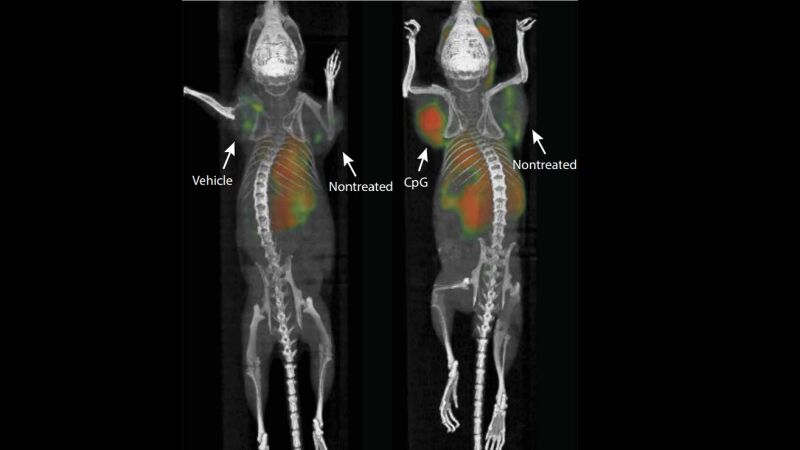

Después de inyectar una combinación de dos refuerzos inmunes directamente en tumores sólidos de ratón, el equipo de investigación ha asegurado que la vacuna ha conseguido eliminar todos los rastros del cáncer específico del cuerpo del animal, incluidas las metástasis que no se habían tratado previamente.

Cuando un sistema inmune detecta células cancerosas en el cuerpo, sus células T atacan el tumor, pero, con el tiempo, el tumor diseña formas de dominar las células inmunes y continúa creciendo. En este experimento, las células T que combaten el cáncer del sistema inmune se rejuvenecieron cuando se inyectó una cantidad de microgramos (una millonésima parte de un gramo) de los dos refuerzos inmunes en un tumor de linfoma de ratón. Esas mismas células luego se movieron desde el tumor que destruyó para encontrar cualquier otro tipo de cáncer idéntico en el cuerpo. Aunque la inyección fue exitosa en la eliminación de los tumores presentes en el ratón, las células T no pasaron a un tumor de cáncer de colon también encontrado en el animal.

El experimento se replicó en otros 90 ratones y logró erradicar los tumores en 87 de ellos, lo que permitió a los investigadores declararlos libres de cáncer. El cáncer recurrió en tres de los animales, pero los tumores retrocedieron luego de otra ronda de tratamiento inmunológico. El estudio también fue exitoso en ratones que tenían tumores de mama, colon y melanoma.